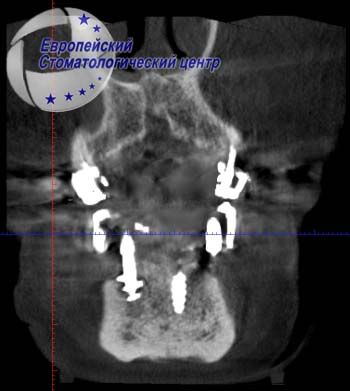

После установки имплантатов проводилась компьютерная томография с целью подтверждения правильности расположения имплантатов (рис. 2, 3).

С целью определения возможности изготовления несъемной ортопедической конструкции с опорой на дентальных имплантатах была проведена компьютерная томография (рис. 1).

В боковых участках, где планируется установка имплантатов, альвеолярный гребень шириной 10,63 мм и высотой 12,60 мм. Расстояние от кортикальной пластинки до нижнечелюстного канала – всего 4,84 мм.

Установка в данном клиническом случае имплантатов в боковом участке в обход нижнечелюстного канала возможно только при условии проведения компьютерной томографии с определением точного расположения канала и последующим изготовлением хирургического навигационного шаблона.

Операция дентальной имплантации была спланирована виртуально в программе DDS-Pro по КТ, сканом моделей и wax-up. В дистальных отделах нижней челюсти были установлены винтовые одноэтапные имплантаты с кортикальной фиксацией в обход нижнечелюстного канала, а в переднем отделе проведена имплантация корневидными имплантатами с винтовой внутрикостной частью. Длина внутрикостной части всех имплантатов – 10 мм, толщина – 3,0 мм.

Таким образом, тщательное планирование хирургического вмешательства с проведением компьютерной томографии обеспечило отсутствие осложнений во время хирургического вмешательства в случае установки одноэтапных корневидных имплантатов: в боковом участке – в обход нижнечелюстного нерва, а в центральном участке – в лунки удаленных зубов.